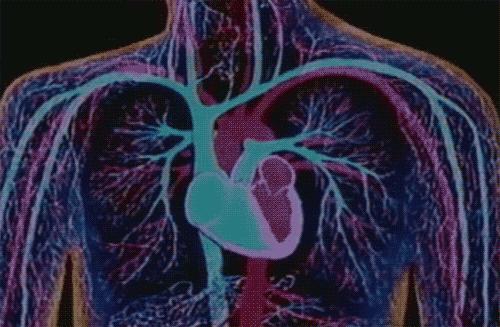

27. 你的第一次心跳,發生在受精卵形成後的第一個月,從此永不停息,直至生命的終點。

28. 心臟這塊拳頭大小、250 克的肌肉,力量卻能把血液推到 1.6 米高度,將血流泵向你最遠的頭部與指尖。

這種跳動每天要進行 10 萬次,一生累計 35 億次,且在晝夜不息、幾乎不允許失誤的條件的下完成,

堪稱壯舉!

❤️

29. 紅細胞在四個月的生命裏,將在你體內循環 15 萬次,爲身體的角角落落運送氧氣。

衰老後的紅細胞會來到脾臟,等待拆解,使珍貴的鐵原子循環利用。